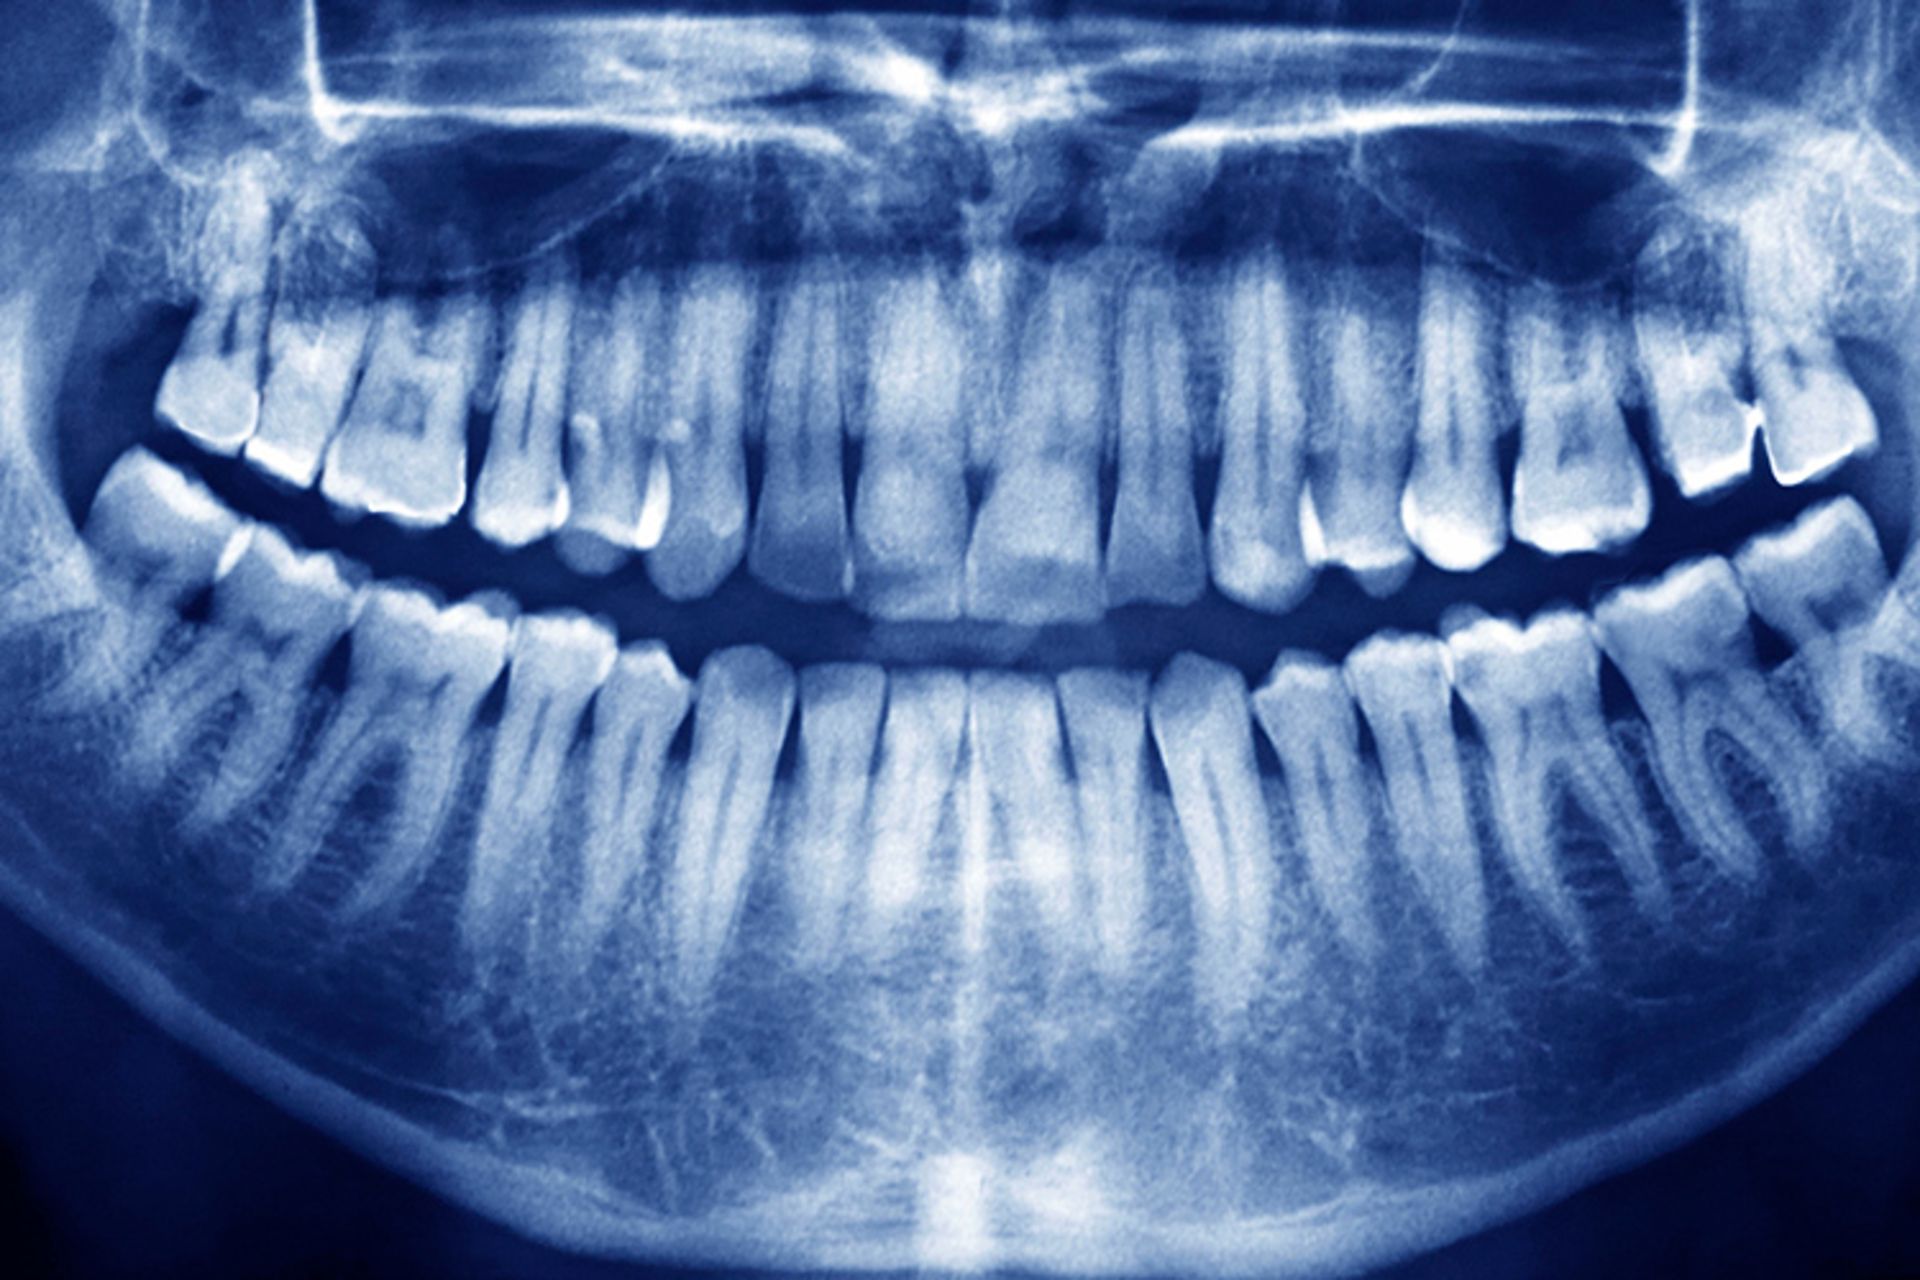

ترمیم دندان های پوسیده با داروی طراحی‌شده برای بیماران آلزایمری

سال گذشته پژوهشگران متوجه شدند که تیدگلوسیب Tideglusib، که در اصل برای بیماری آلزایمری ساخته شده است، موجب بهبود مکانیزم رشد مجدد و طبیعی دندان در موش می‌شود؛ به شکلی که به دندان اجازه می‌دهد تا حفره‌های خود را ترمیم کند.

تیدگلوسیب با تحریک سلول‌های بنیادی موجود در مغز دندان که منبع تولید عاج دندان تازه هستند، بر ترمیم دندان اثر می‌گذارد. عاج دندان ماده‌ای معدنی واقع در زیر مینای دندان است و به‌علت وجود پوسیدگی دندانی، از بین می‌رود. دندان‌ها تنها تحت شرایطی معین به‌تنهایی و بدون کمک بیرونی، توانایی بازتولید عاج را دارند. مغز دندان باید در معرض عفونت (مانند پوسیدگی) یا ضربه قرار گیرد تا تولید عاج را سرعت ببخشد.

اما حتی در چنین شرایطی، دندان تنها می‌تواند به‌صورت طبیعی لایه‌ای بسیار نازک را بسازد و این میزان برای ترمیم حفره‌های ایجاد شده در اثر پوسیدگی که عموما عمیق هستند، کافی نیست. تیدگلوسیب به‌دلیل خاموش کردن آنزیم GSK-3 که مانع ایجاد عاج دندان می‌شود، برآیند عمل دندان برای بازسازی را تغییر می‌دهد.